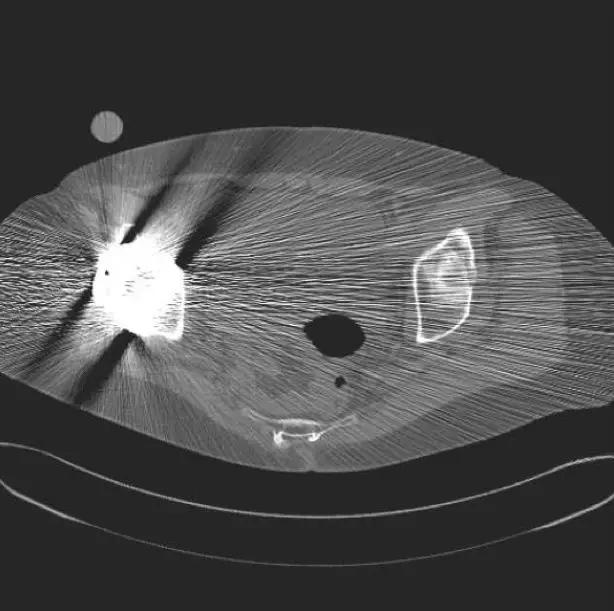

金属伪影是由体内的金属异物引起的放射状伪影,这是因为金属异物与周围组织密度相差太大。其周围会出现带状或线状高、低密度伪影。消除方法:取出后扫描,或者避开扫描。

(金属伪影)